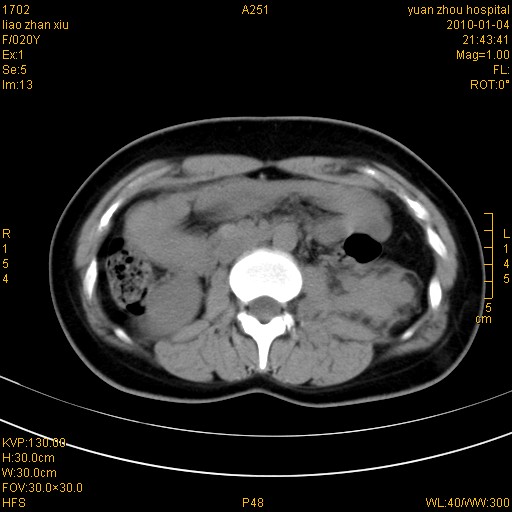

标题: CT23985:F20Y 外伤典型病例 [打印本页]

标题: CT23985:F20Y 外伤典型病例

左肾挫伤,包膜下积血,l3、4左侧横突多发骨折。

2、l3、4左侧横突多发骨折;

气死我了,明明l1、2,为什么都说3、4.

左肾挫伤,包膜下积血,L1、2、3、4左侧横突多发骨折。